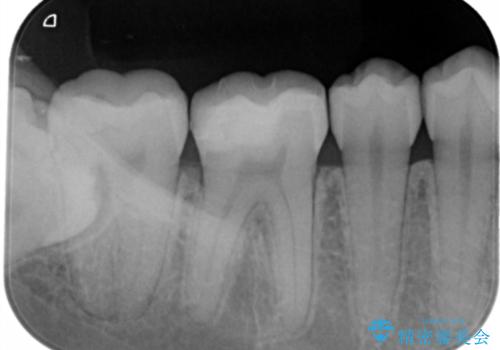

- 右下大臼歯の保険材料劣化に伴う虫歯の治療を希望された患者さまです。

審美性や精度の高い治療を希望されたので切削量や形態を考慮し、セラミックインレーでの治療を選択しました。

保険治療で使用される材料は劣化しやすく直下で虫歯が進行していることが多いです。

今回の患者さまは遠心部の虫歯が深かったのでCRで裏層した上で形成・印象を行いインレーセットを行っています。